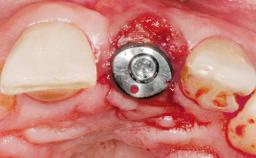

| Placement Protocol | Immediate implant placement |

| Loading Protocol | Immediate |

| Provisional Implant-Supported Prosthesis | Prosthodontic margin < 3 mm apical to mucosal margin Prosthodontic margin < 3 mm apical to mucosal margin |